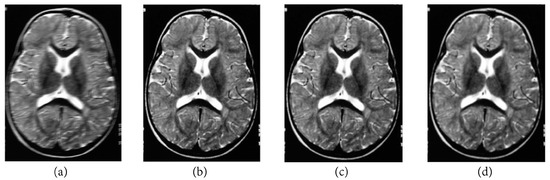

The following numerical results are proposed: Figure 2 presents the original grayscale images for (a) X-ray film of the brain and (b) X-ray film of the right shoulder. Figure 3 and Figure 6 are blurred X-ray films of the brain and the right shoulder images with filtering M i x in the part of degradation of Figure 1. In this example, we set N = 4 . So, we have M 1 x , M 2 x , M 3 x , and M 4 x . Figure 4a, X-ray films of the brain and the right shoulder images were obtained via Theorem 2. Figure 4b, X-ray films of the brain and the right shoulder images were obtained via Theorem 3.1 in [16] (Khuangsatung and Kangtunyakarn’s method). Figure 9 is an X-ray film of the brain image that was recovered via the proposed method that was tuned for the parameter λ.

Figure 3. Blurred X-ray film of the brain image with filtering M i x by (a) M 1 x , (b) M 2 x , (c) M 3 x and (d) M 4 x .

Figure 4. (a) X-ray film of the brain image obtained via Theorem 2 and (b) X-ray film of the brain image obtained via Theorem 3.1 in [16].